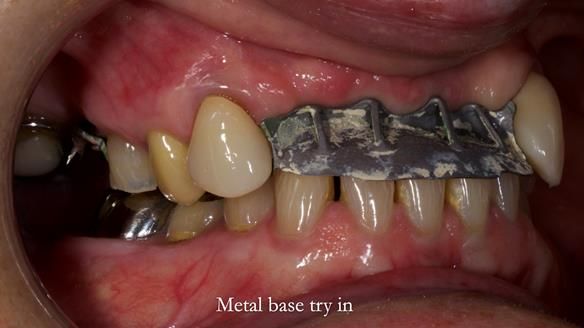

This is one of those cases that reminds me why I love removable prosthodontics. Pam was an absolute joy to treat — we were on the same page throughout. Her old upper flexible denture was loose, uncomfortable, and unaesthetic. We replaced it with a carefully designed metal-based upper partial denture/splint and new porcelain-bonded-to-zirconia (PBZ) crowns for the canines. The result is stable, comfortable, and natural-looking.

- Diagnosis and plan – Flexible upper denture ill-fitting with poor stability, retention, and appearance. Plan: metal-based upper partial denture/splint with lighter porcelain-bonded-to-zirconia crowns on UR3 and UL3.

- Metalwork framework try-in – to verify fit, path of insertion, and support.